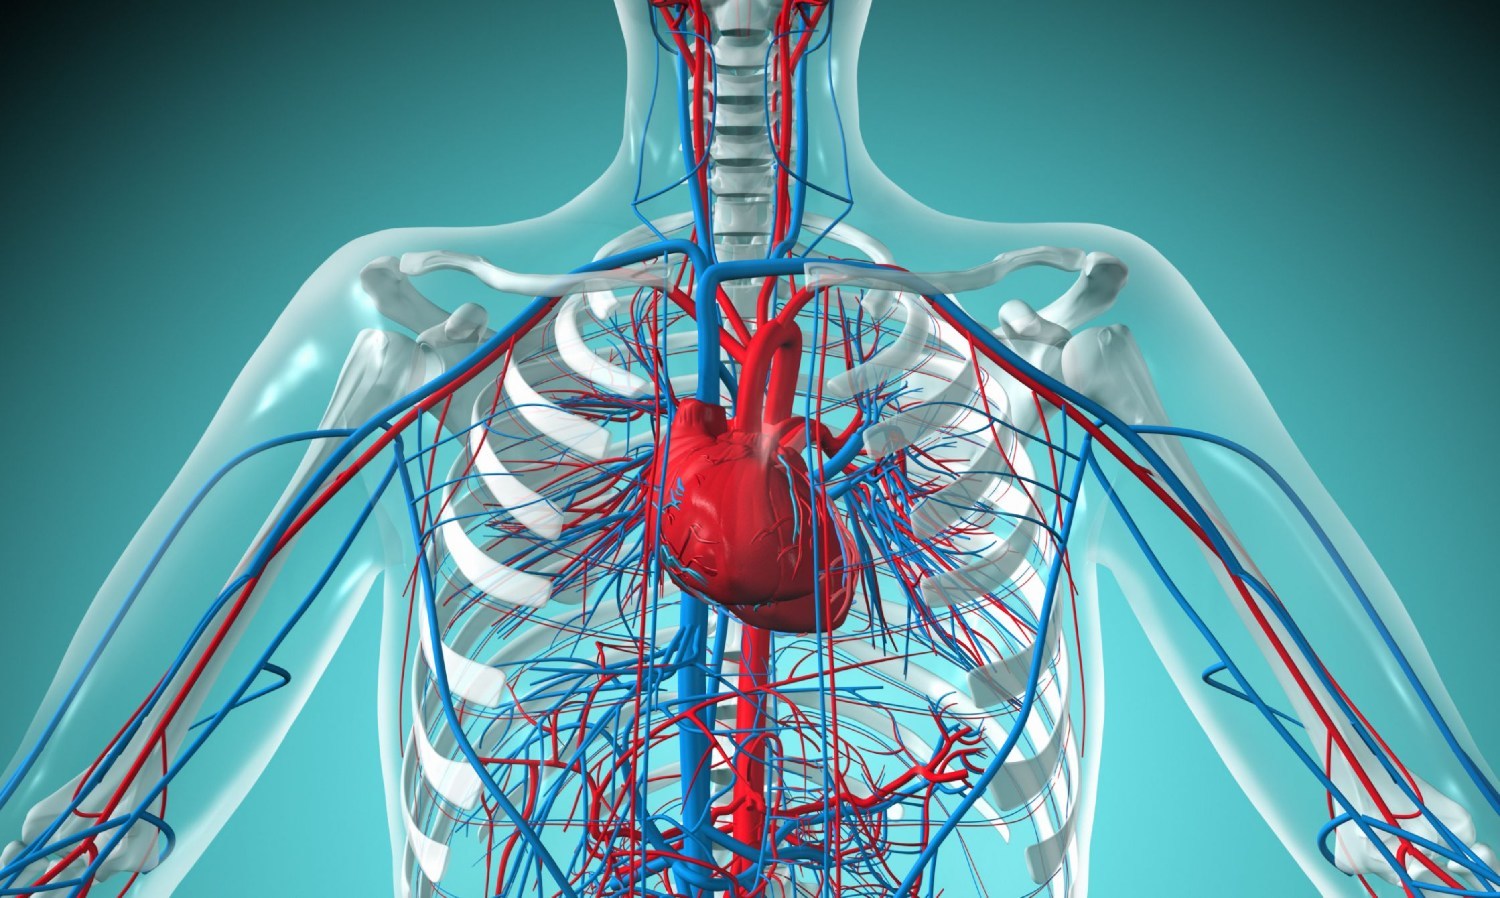

Çipslər, qəlyanaltılar, konservlər və s. Kardioloq izah etdi ki, duz ürəyə və qan damarlarına əlavə, lazımsız yük yaradır.